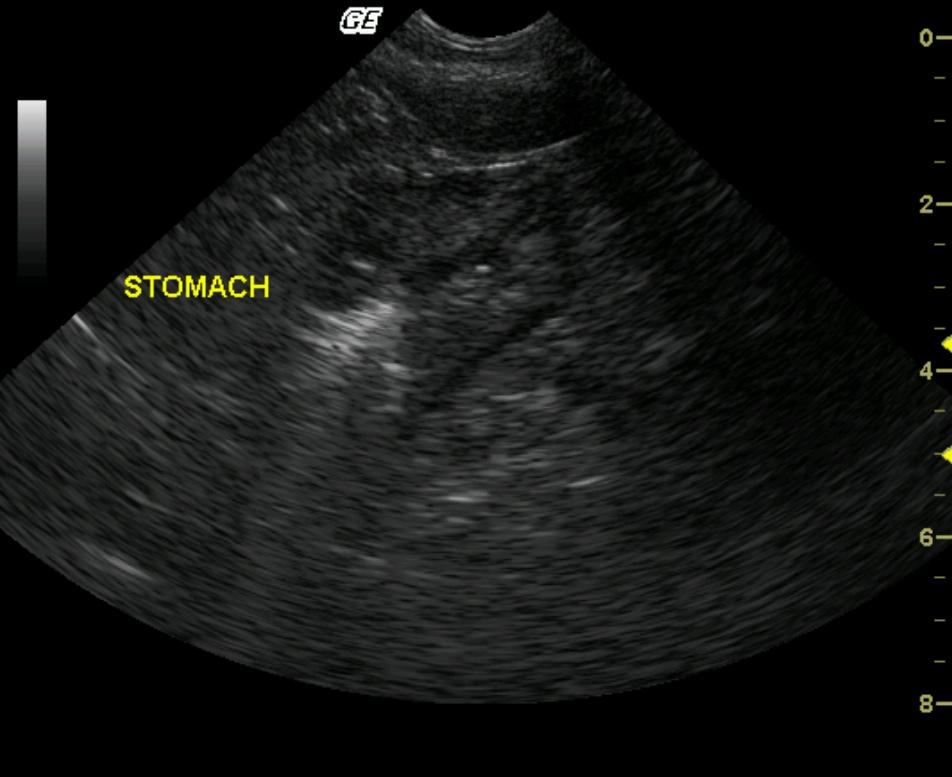

R/O multifocal mucosa mineralization consistent with chronic inflammatory gastropathy. Neoplasia is considered less likely.

Marked, circumferential pyloric wall thickening with altered wall layering is present. A majority of the thickening is involving the submucosal layering. Small, pinpoint and linear echogenic foci are associated with the mucosal layer.